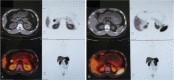

Diagnosis: Examinations in the local hospital did not reveal any pancreatic lesion. After admission, a fasting test and a 5-hour oral glucose tolerance test (OGTT) suggested a diagnosis of endogenous hyperinsulinemic hypoglycemia. Enhanced volume perfusion computed tomography (VPCT) revealed 2 nodules in the tail of the pancreas, a nodule in the gastric antrum, and a nodule in the hilum of the spleen. To differentiate which nodule was responsible for hypoglycemia, we performed 68Ga-Exendin-4 PET/CT and 68Ga-DOTATATE PET/CT which helped to make a conclusive diagnosis that the lesion in the gastric antrum was an ectopic insulinoma.

Conclusions: This case shows that 68Gallium-exendin-4 PET/CT is useful for precise localization and thereby successful treatment of insulinoma, especially for occult insulinomas and those derived from an ectopic pancreas.